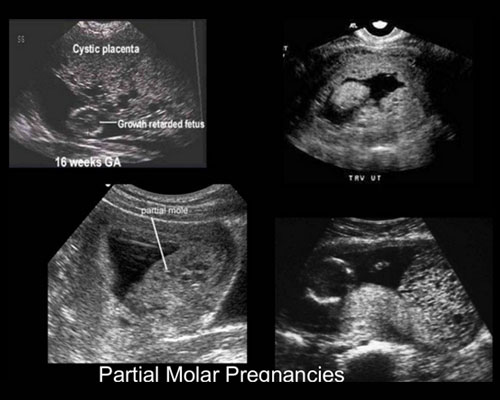

A 32yrs old woman came to our hospital with a tested urine preganancy card which indicates positive. then I go through scan, it shows she has vesicular mole at her uterus. her b-hcg level is 5,814.9,Here I shared about the types of molar pregnancy, symptoms.

Symptoms of a molar pregnancy are:

• Partial molar pregnancy. There is an abnormal placenta and some fetal development.

• Complete molar pregnancy. There is an abnormal placenta and no fetus.

• Abnormal growth of the uterus, either bigger or smaller than usual

• Nausea and vomiting that may be severe enough to require a hospital stay

• Vaginal bleeding during the first 3 months of pregnancy